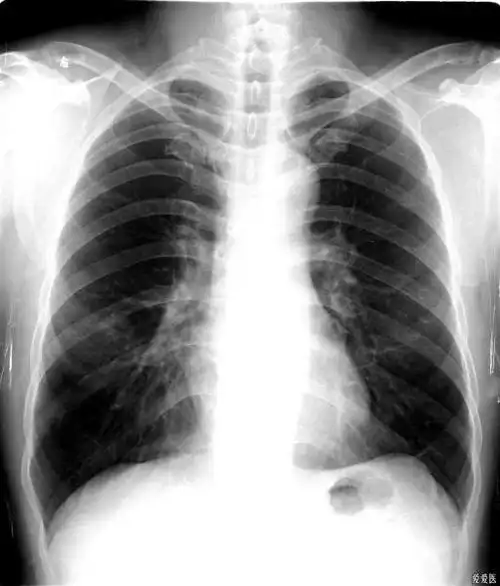

肺科视界:右肺中叶综合征

右肺中叶改变

但是两个不同的病,右上肺大的,这个是一个结核瘤,右肺中叶这个小一点